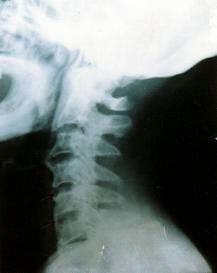

正常的时候,我们颈部的骨骼是这样排列的,间距差不多,脖子后面应该也是平滑的。

但是坐姿不正确的时候,因为肌肉长期拉长,骨头间距也会被拉宽,但时候要矫正就不容易了。

姿势不正确的人,把颈部后仰的时候,脖子后面会出现很深的颈纹,脂肪在颈和肩的交界处堆积,出现一个大肉团。